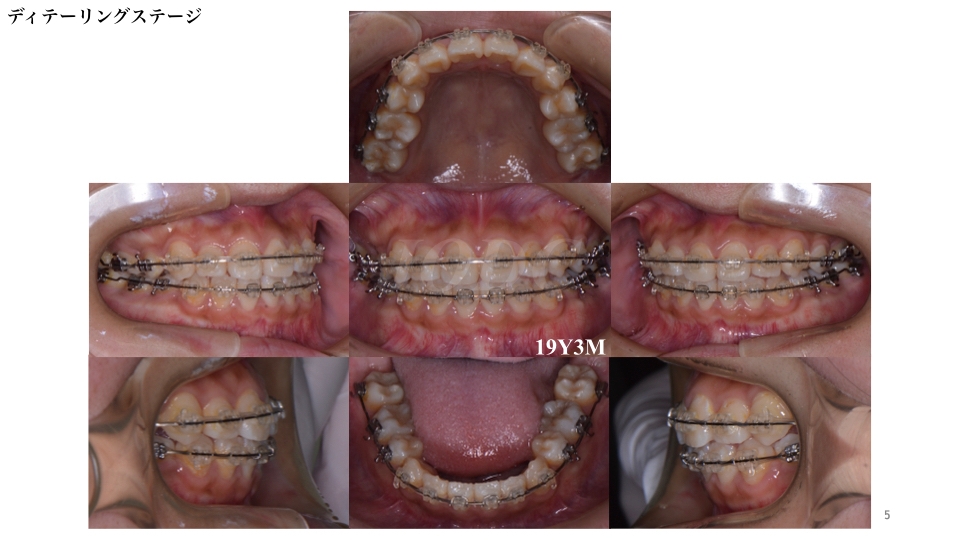

個々の歯の詳細な配列を行うディテーリングステージです。